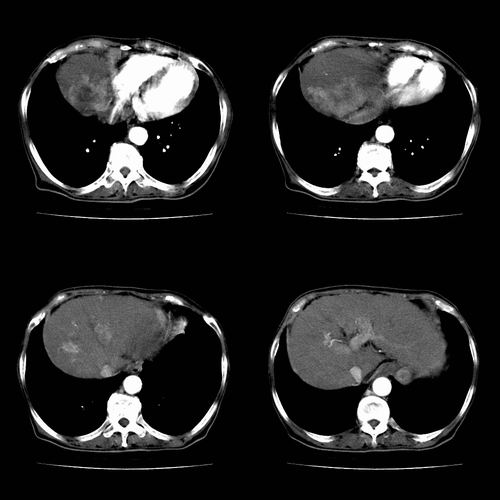

图片非常漂亮!肝内病灶符合较典型肝癌的强化方式,速升速降,其内可见坏死,腹膜后示肿大淋巴结融合成团,包绕腹主动脉、腹腔干动脉、肠系膜动脉。右肾小囊性病灶,未见明显强化。

诊断:肝癌并腹膜后淋巴结转移。

肝癌伴门静脉及下腔静脉癌栓形成,腹膜后淋巴结转移.

肝癌伴腹膜后淋巴结转移,肝硬化伴脾大,好像没有发现门静脉及下腔静脉瘤栓形成.

1、肝右叶肝癌,后腹膜淋巴结转移(包绕腹腔干及肠系膜上动脉,推压门静脉、下腔静脉及胰头)

2、肝硬化、脾肿大

3、右肾小囊肿

1、肝硬化,脾肿大

2、肝癌,动静脉瘘(动脉期门静脉内造影剂进入)

3、后腹膜淋巴结转移,下腔静脉推移